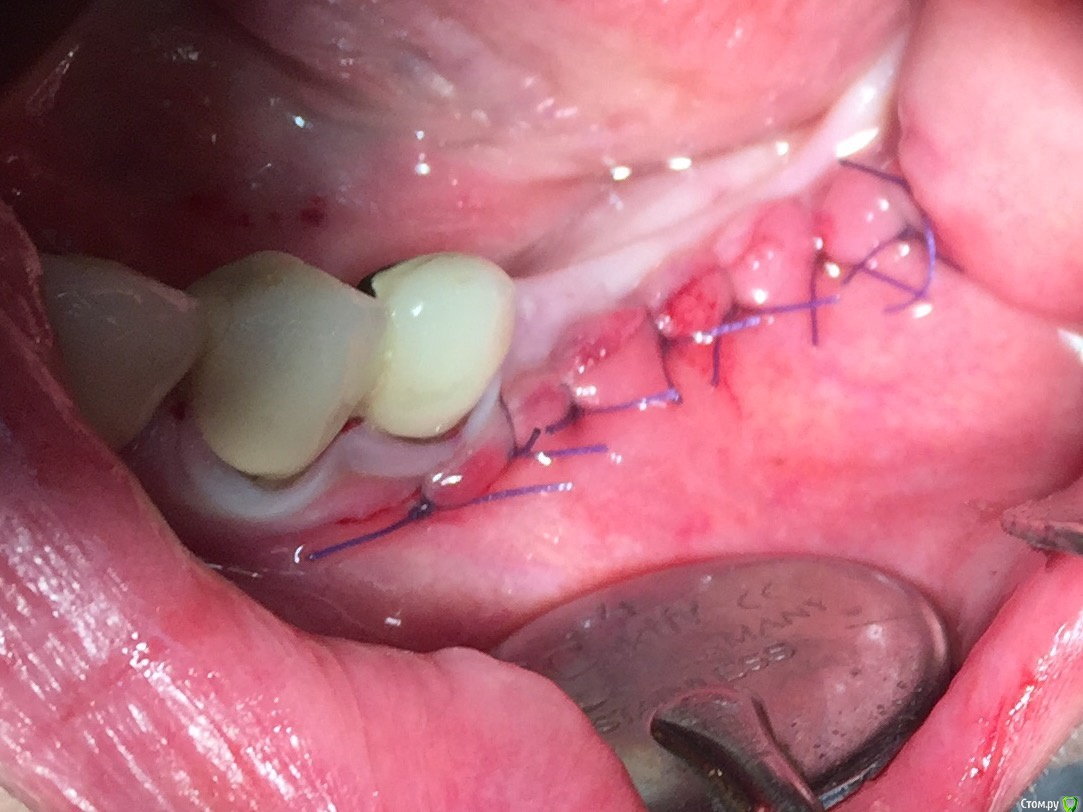

Глеб Митрофанов Опубликовано 16 января, 2016 Автор Поделиться Опубликовано 16 января, 2016 Скажите, пожалуйста, чем укрылись на 5-м фотоА-PRF Ссылка на комментарий

Глеб Митрофанов Опубликовано 16 января, 2016 Автор Поделиться Опубликовано 16 января, 2016 Винты 1,5 мм самосверлящие,Конмет?Длина какая? L пластины длинные? Да , винты 1,5 мм самосверлящие конметовские длина верхние 5 мм , нижние 4 мм , пластины не длинные , по одному сегменту отпилил еще 1 Ссылка на комментарий